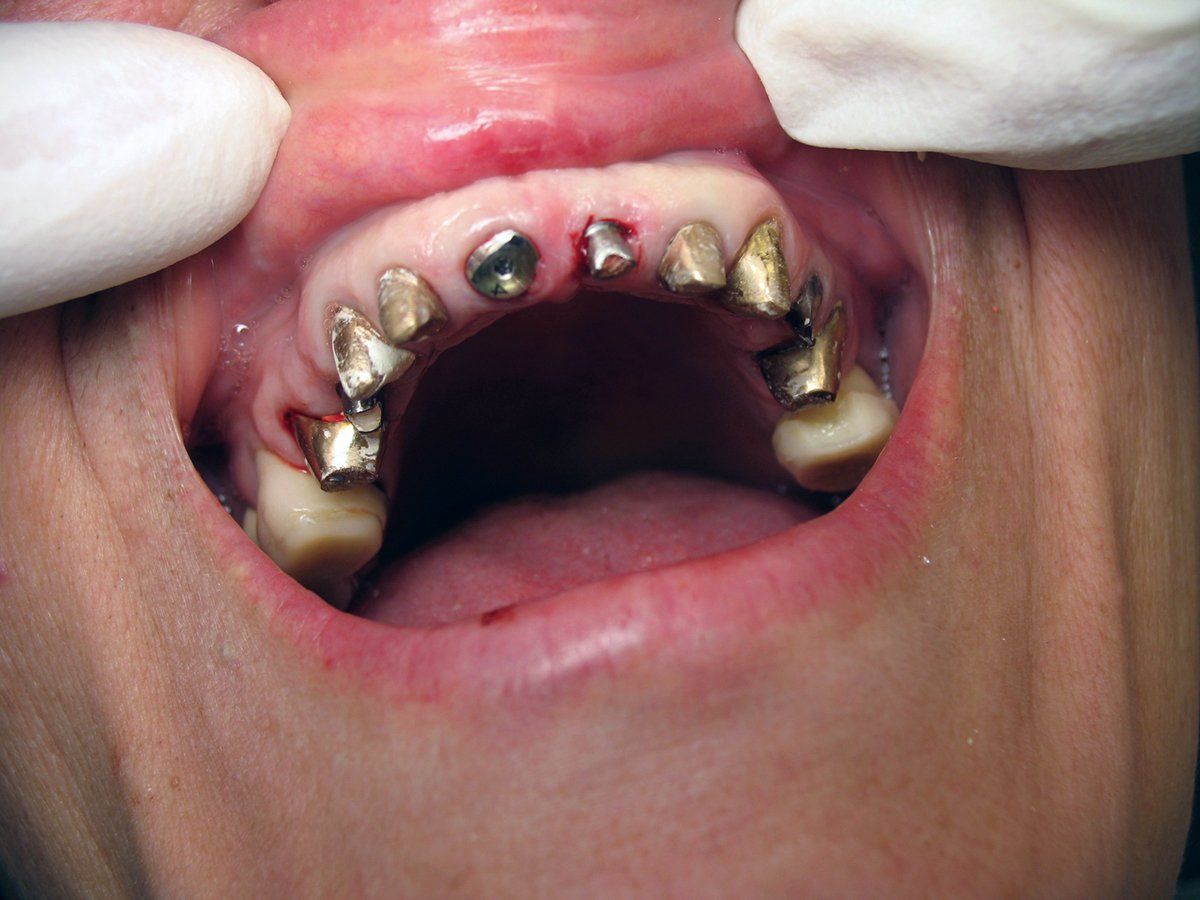

One day a 50 year-old patient and dentist friend of mine, (who already has multiple dental implants) came to my office and presented with a non-restorable fractured tooth number 8 (Figure 1). As you can see from the photograph, this looked to be a complicated extraction. As always, my treatment plan consists of proper imaging. With dental implant cases it usually involves the i-CAT. (Figure 2)

The primary challenge was to remove tooth number 8, while maintaining the soft tissue and bone intact. As I have mentioned in previous articles, I will strategically plan out the entire case before beginning any procedures. The plan was to extract tooth #8 and place an immediate implant. Since there was no root to grab on to, and lifting a flap would compromise the buccal bone, I decided to utilize a new instrument on the market called Benex® Control, an atraumatic tooth extractor by Meisinger USA. I feel one has to have state-of -the-art tools and technology at their disposal for just the right application. This case was an ideal case for the Benex® Extractor. This device works like magic for removing single roots without lifting a flap or cutting bone.